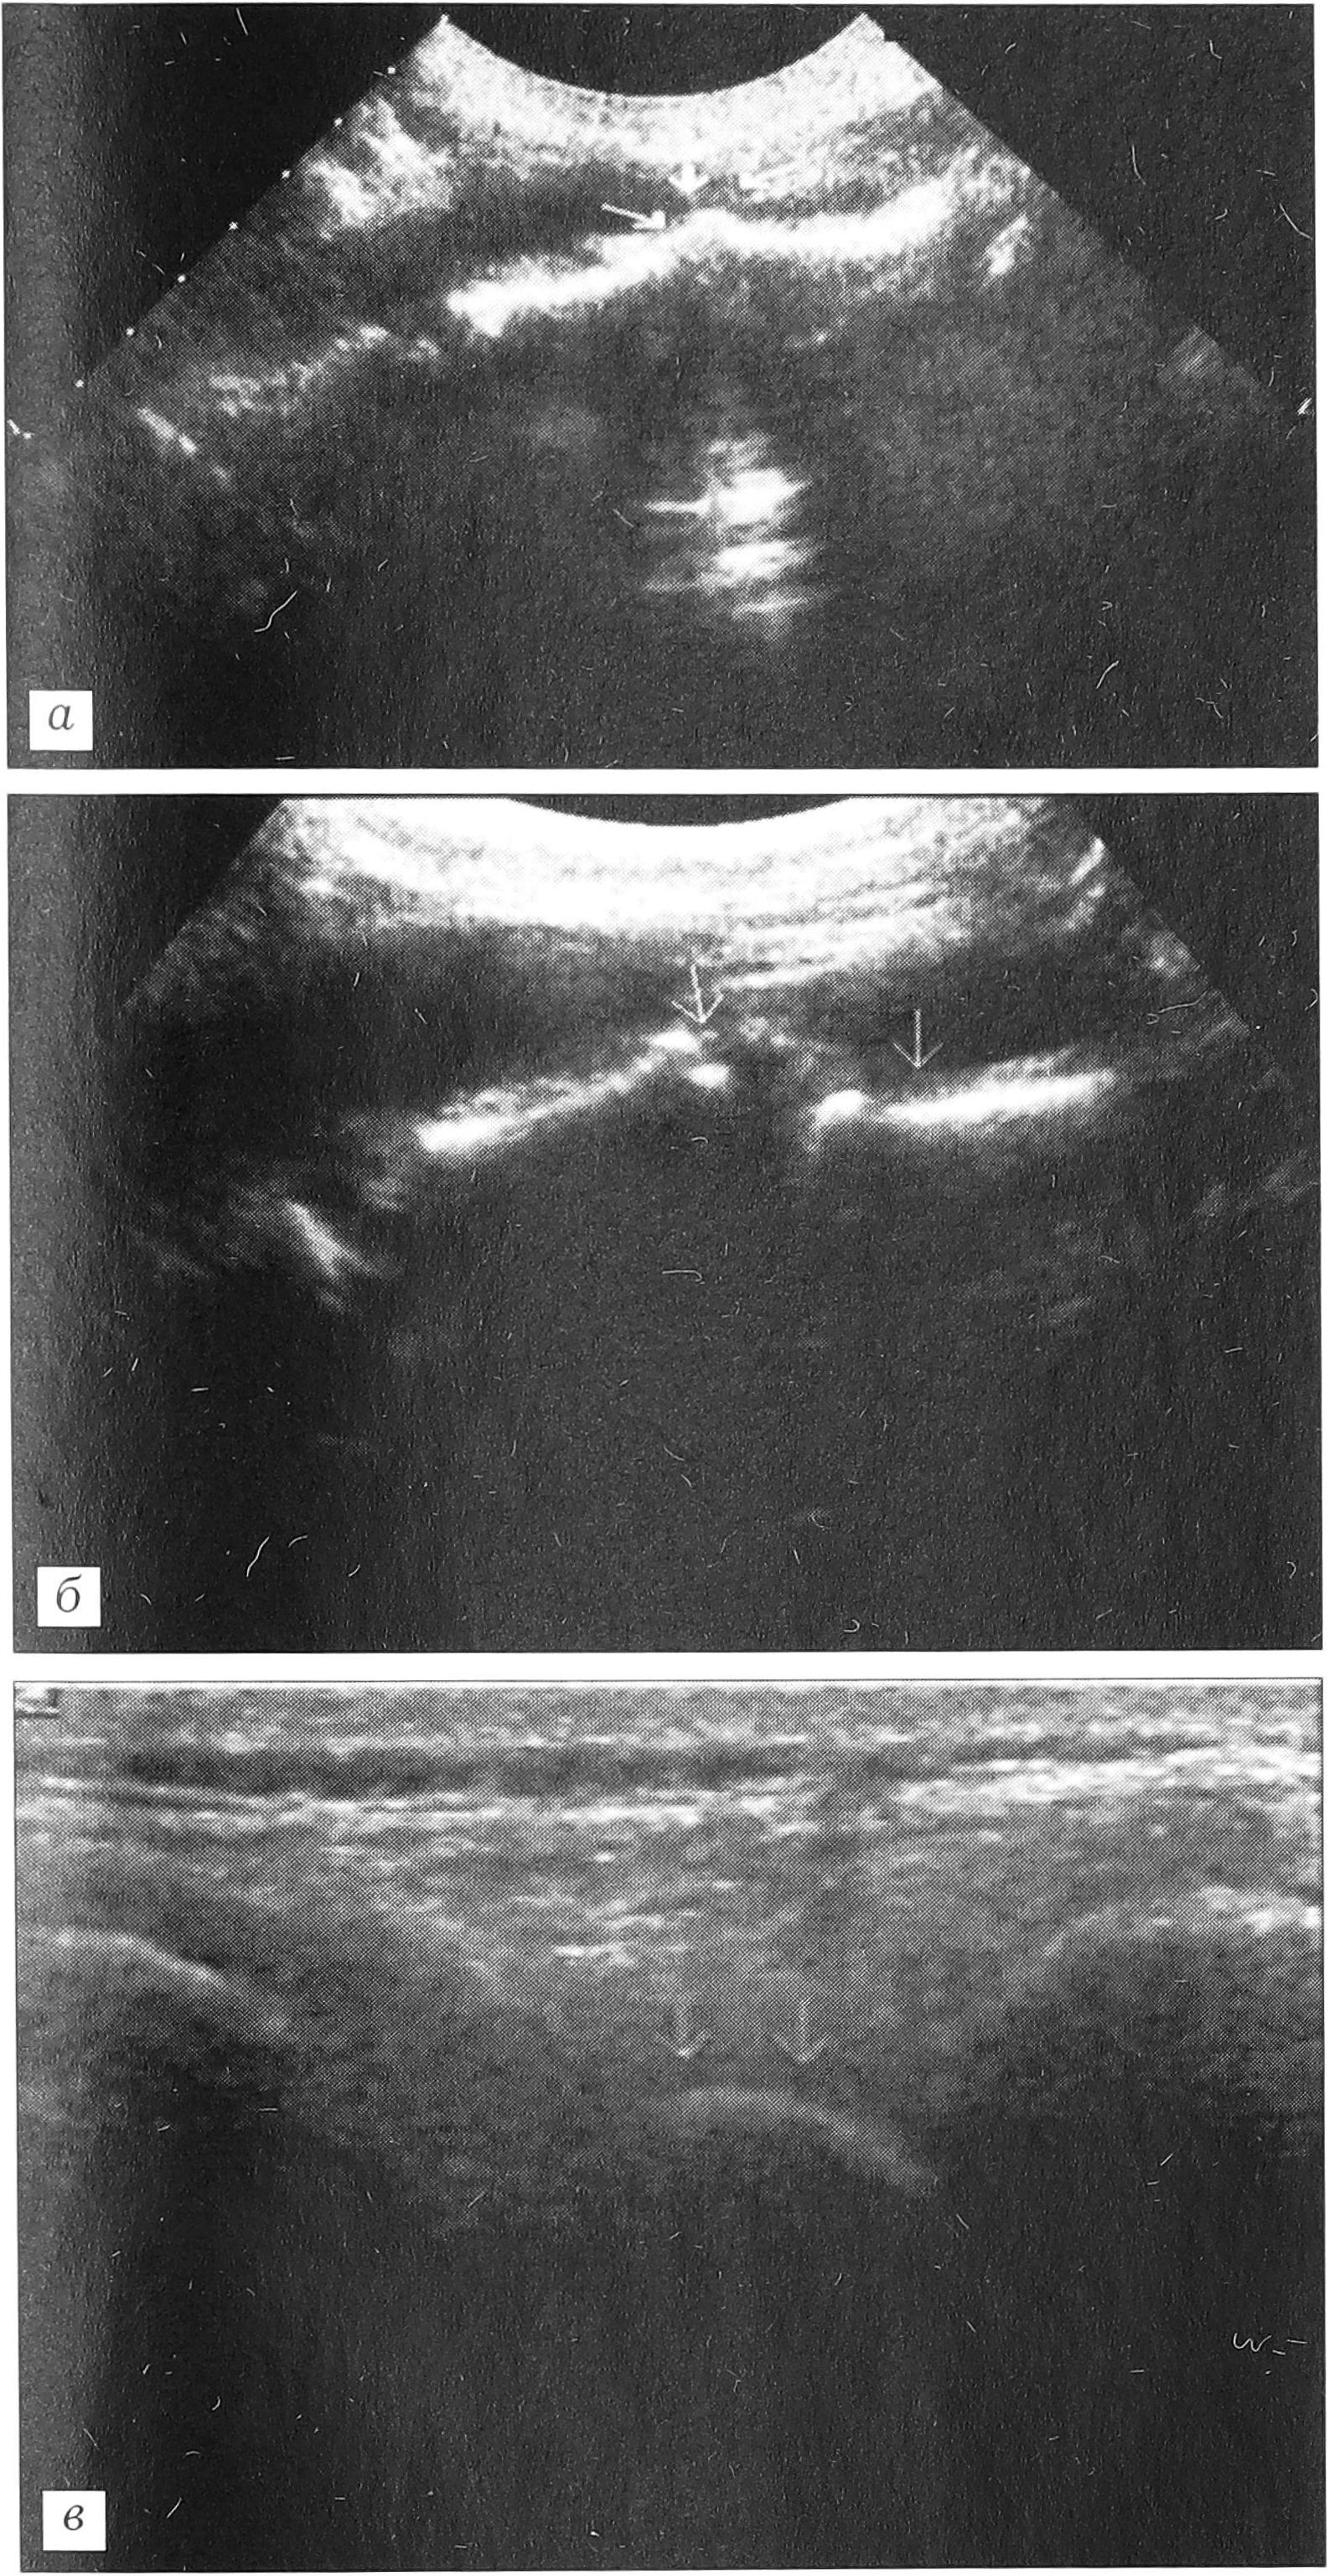

Нестабильность позвоночного сегмента. При сонографии нестабильность позвоночного сегмента выявлена у 11 пациентов со спондилолизом нижнепоясничных позвонков. Она определялась при исследовании позвоночника из переднего и заднего доступов с проведением функциональных проб. Критериями, подтверждающими наличие нестабильности, являлись: 1) смещение передних границ межпозвонковых дисков (рис. 7, а); 2) ступенеобразное смещение переднего контура тел позвонков при сагиттальном сканировании из переднего доступа, изменяющееся при проведении функциональных проб (рис. 7, б); 3) смещение задних границ остистых отростков при функциональных пробах (рис. 7, в).

Рис. 7. Ультрасонограммы при разных степенях нестабильности позвоночного двигательного сегмента. a — смещение передних границ межпозвонковых дисков; б — ступенеобразное смещение переднего контура тел позвонков; в — смещение задней границы остистого отростка смещенного кпереди позвонка.

В начальных стадиях нестабильности позвоночного сегмента, когда имело место только пролабирование переднего отдела диска, кровоток не менялся. При значительной нестабильности, подтвержденной функциональными пробами, определялось усиление кровообращения, выражавшееся в появлении большого числа сосудов, врастающих в диск.